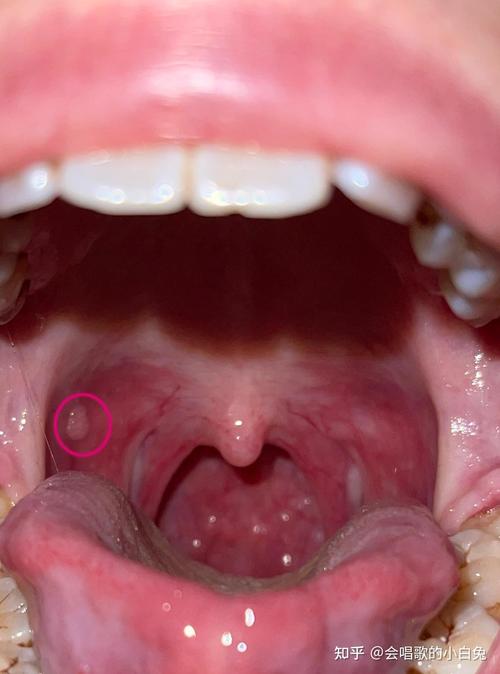

口腔乳头状瘤

- 原因:由人乳头瘤病毒(HPV)感染引起的良性增生。

- 特点:

- 表面呈菜花状或桑葚状,有许多细小的指状突起。

- 通常为白色或粉红色,质地较韧。

- 一般无疼痛感。

(图片来源网络,侵删)